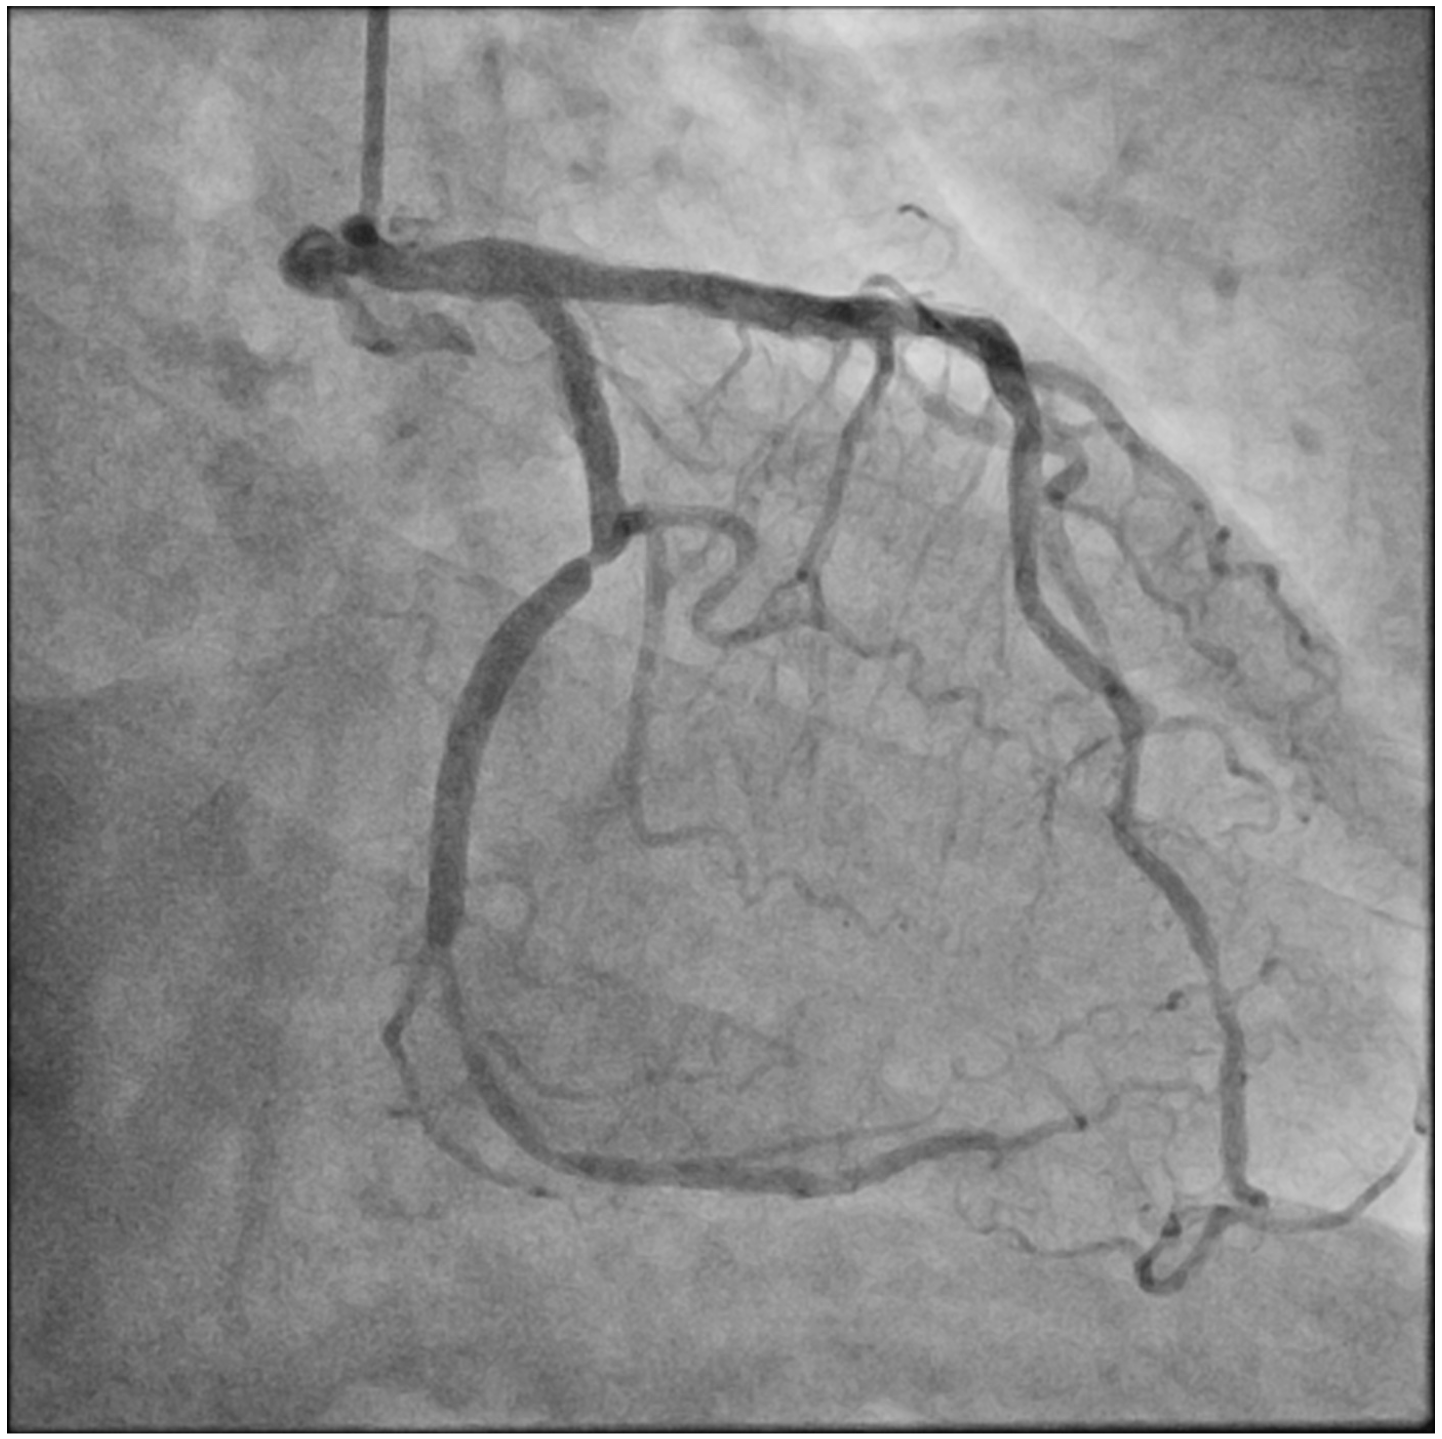

Distal small balloon retrieval was unsuccessful (Figure 1D). With the help of the Balloon-Assisted Guide-extension (BAG) system, the stent could be optimally positioned at the proximal LCX lesion by forward pushing with a 6-Fr Guideliner V3 catheter (Teleflex) and backward pulling by the small balloon (Figure 1E and F; Video). It was then deployed by sequential balloon dilatation with good expansion (Figure 1G and H). Another 2.5 x 24-mm DES was deployed at the distal LCX, which gave an excellent final angiographic result (Figure 1I and J).